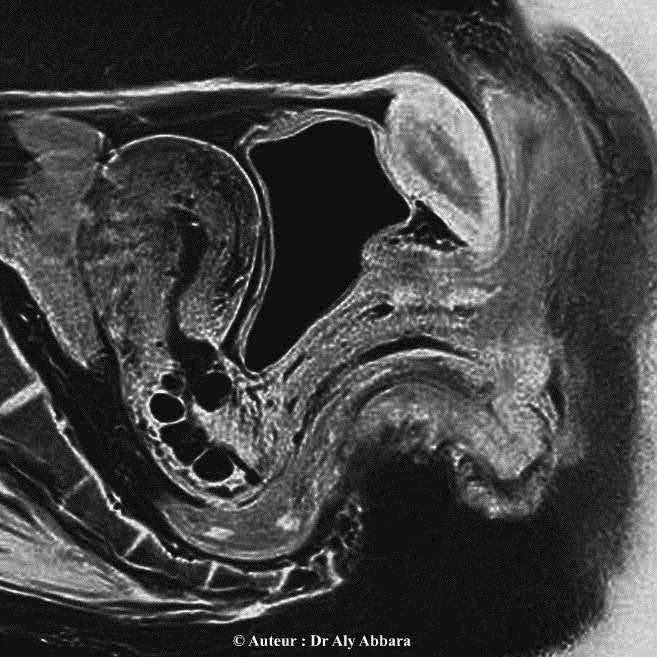

Anatomie du pelvis - coupe sagittale médiane - utérus, adénomyose, kystes de Naboth, vagin, vessie et rectum

Vagin : ses rapports anatomiques avec les organes avoisinants

(coupe sagittale médiane du pelvis - Imagerie par résonance magnétique - IRM)

(accessoirement sur cette image, l'utérus est marqué par la présence d'une lésion adénomyosique sur la paroi postérieure du corps utérin = épaississement fibreux de la paroi ; puis au niveau du col utérin on observe la présence de multiples kyste de Naboth) .

Le vagin est situé dans la cavité pelvienne, entre la vessie et l'urètre en avant et le rectum en arrière ; il se fixe en haut sur le col utérin (عنق الرحم) qui fait saillie dans sa cavité mais les parois vaginales restent séparées du col utérin par un cul-de-sac (رتج) annulaire (ou fornix vaginal) divisé en quatre segments (deux culs-de-sacs latéraux, droit et gauche; un cul-de-sac antérieur et un cul-de-sac postérieur).

• Morphologiquement le vagin est plus étroit au niveau de son tiers inférieur, près de la vulve, puis il s'élargit au niveau de son tiers moyen et surtout au tiers supérieur, cette étroitesse relative dans la portion vaginale située près de son entrée vulvaire est due à la présence des fuseaux musculaires des muscles releveurs de l'anus qui encerclent cette partie du vagin en arrière et bilatéralement. Cet encerclement musculaire donne au vagin une forme coudée ou arquée, donc en position décubitus dorsal, sur un plan sagittal médian, la partie basse du vagin est oblique (de l'arrière en bas vers l'avant en haut), la partie haute du vagin se dirige vers l'arrière. L'angle formé (ou l'arc) par les deux axes du vagin est un angle obtus, ouvert vers le bas (en position allongée sur le dos) et sa valeur est égale à environ à 140 degrés.

L'orifice externe du col utérin est posé sur la paroi postérieure du fond du vagin car l'axe du col est presque vertical sur la paroi vaginale postérieure.